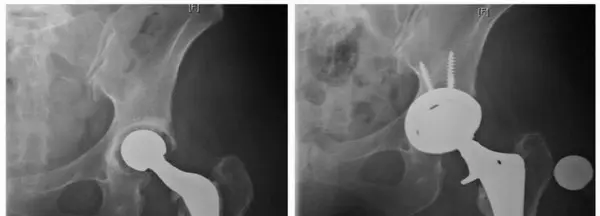

- يوضح الشكل 5-1 صور الأشعة السينية لمريضة خضعت لمراجعة مفصل الورك بعد عدوى. كان من الممكن أن يمنع استخدام بضع المدور الكبير الممتد وضع الغرسة في وضع تقوس (varus).